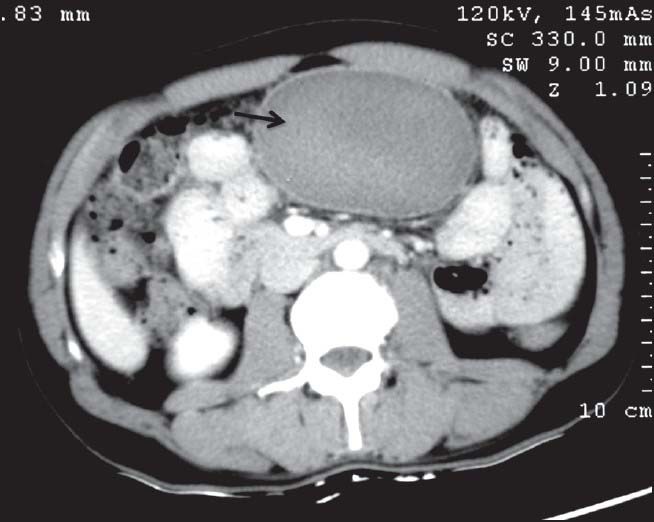

| Figure 2:Ileal gastrointestinal stromal tumor in a 45-year-old male — axial contrast-enhanced computed tomography image showing heterogeneously enhancing exophytic mass lesion (black arrowhead) arising from ileal loop causing mild aneurysmal dilatation (white arrowhead)

| Figure 2:Ileal gastrointestinal stromal tumor in a 45-year-old male — axial contrast-enhanced computed tomography image showing heterogeneously enhancing exophytic mass lesion (black arrowhead) arising from ileal loop causing mild aneurysmal dilatation (white arrowhead)